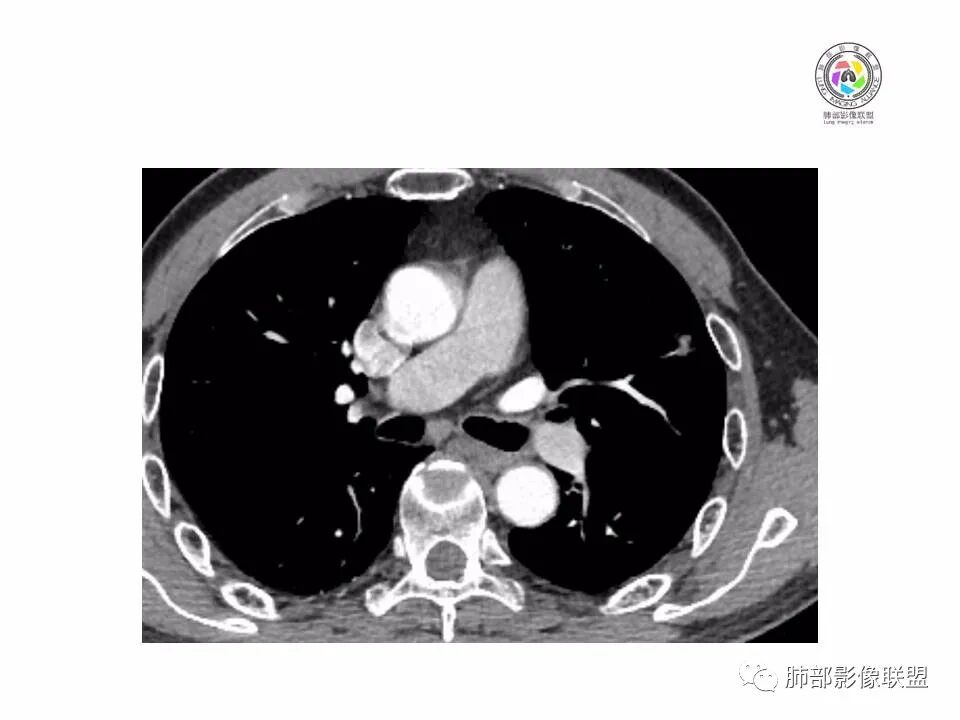

左肺形态不规则结节,边缘收缩,毛刺,有月牙铲,纵隔窗比肺窗小,不密实,近段血管与病灶相连,强化不明显,老年男性,综合考虑,恶性,腺癌,鉴别炎性结节。建议穿刺。

左上肺结节分叶,边缘毛糙,小空泡可能,血管集束,月牙,纵隔窗面积小于肺窗,有磨玻璃成份,有强化,老年男性,白细胞高,恶性的征象都有,但磨玻璃的形态和边界不好评估,实性为主,看形态和边缘局部较散缺乏饱满感,顶着压力反着来猜炎性可能大。复查不消失会考虑腺癌或黏液腺癌。

老年男性,肺气肿背景,左肺上叶实性结节,边界清,边缘平直为主,细长毛刺,较明显强化,考虑炎性病灶,隐球?

老年男性,左肺上叶结节,边缘可见长毛刺、较软,并可见分叶,周围可见清楚磨玻璃密度,内可见空泡征,增强后呈均匀强化,良恶性征象都有,感觉收缩力不强,化验白细胞偏高,建议抗炎治疗后复查除外腺癌。

老年男性,左肺上叶混合密度结节,空泡,分叶,血管集束,有强化,考虑腺癌;细长软毛刺,血管走行自然,边缘有平直收缩,白细胞高,肿标正常,考虑炎性结节。猜炎性结节,鉴别腺癌。

患者老年男性,体检发现。查癌胚抗原不高。血常规血象升高。胸部CT:肺气肿背景,左肺上叶近胸膜下实性结节,边缘光滑,边界清楚,可见毛刺、血管集束、月牙铲征象,增强不明显,内可见低密度区,综合考虑恶性病变,腺癌可能大,鉴别结核及炎性结节。

老年男性,左肺上叶结节,周围浅分叶伴磨玻璃影,有血管相连,月牙铲。纵隔见肿大淋巴结,但白细胞高。腺癌首先,需排除炎性假瘤。抗炎治疗后复查。

老年男性,体检发现左肺结节,分叶、脐凹、月牙铲及月牙铲附近有边缘清楚的磨玻璃影,上述征像均指向恶性肿瘤,有疑问的地方:毛刺软无力,无胸膜牵拉及白细胞计数升高。整体是腺癌,需要抗议后复查以排除炎性病变。

图片有限,左肺上叶结节病灶,有张力,有收缩及小泡征,边缘可见月牙征,周围长毛刺及血管集束征,增强目测有中度以上强化,首先考虑恶性病变,腺癌。